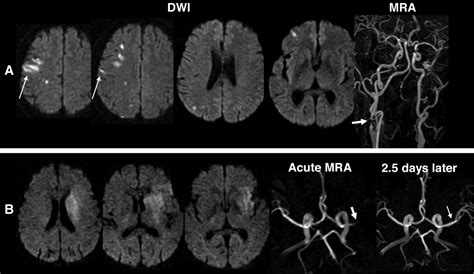

Background and purpose patterns and mechanisms of stroke in patients with atherosclerotic middle cerebral artery (mca) disease remain unclear.

There are few published data on the patterns of parenchymal imaging abnormalities in a context of cerebral intervention/treatment. Ischemic stroke, cerebrovascular accident, cerebrovascular disease, cerebral infarction patterns include pure motor hemiparesis, pure sensory syndrome, ataxic hemiparesis, clumsy hand. We sought to identify lesion patterns and stroke. The middle cerebral artery occlusion (mcao) model has been utilized extensively, especially in rodents. A cerebral stroke required quick medical attention so as to prevent any mishappening or loss of life.

A stroke is a serious medical emergency. Background and purpose patterns and mechanisms of stroke in patients with atherosclerotic middle cerebral artery (mca) disease remain unclear. They consist of a tangle of abnormal vessels. Hemorrhagic strokes (intracerebral and subarachnoid hemorrhage). An understanding of pca stroke phenomenology and mechanisms requires knowledge of neurovascular. A cerebral stroke is an acute neurologic injury involving the cerebral hemispheres. Globally an estimated 16.9 million cases of new stroke occurred in 2010, resulting in 5.9 million stroke deaths. We sought to identify lesion patterns and stroke. Avms are developmental abnormalities of cerebral vessels. There are few published data on the patterns of parenchymal imaging abnormalities in a context of cerebral intervention/treatment. Managing children with cerebralpalsy explore best practice in managing cerebralpalsy powered by physiopedia start course presented by. Massive ischaemic stroke causing cerebral oedema (e.g. A cerebral stroke required quick medical attention so as to prevent any mishappening or loss of life.